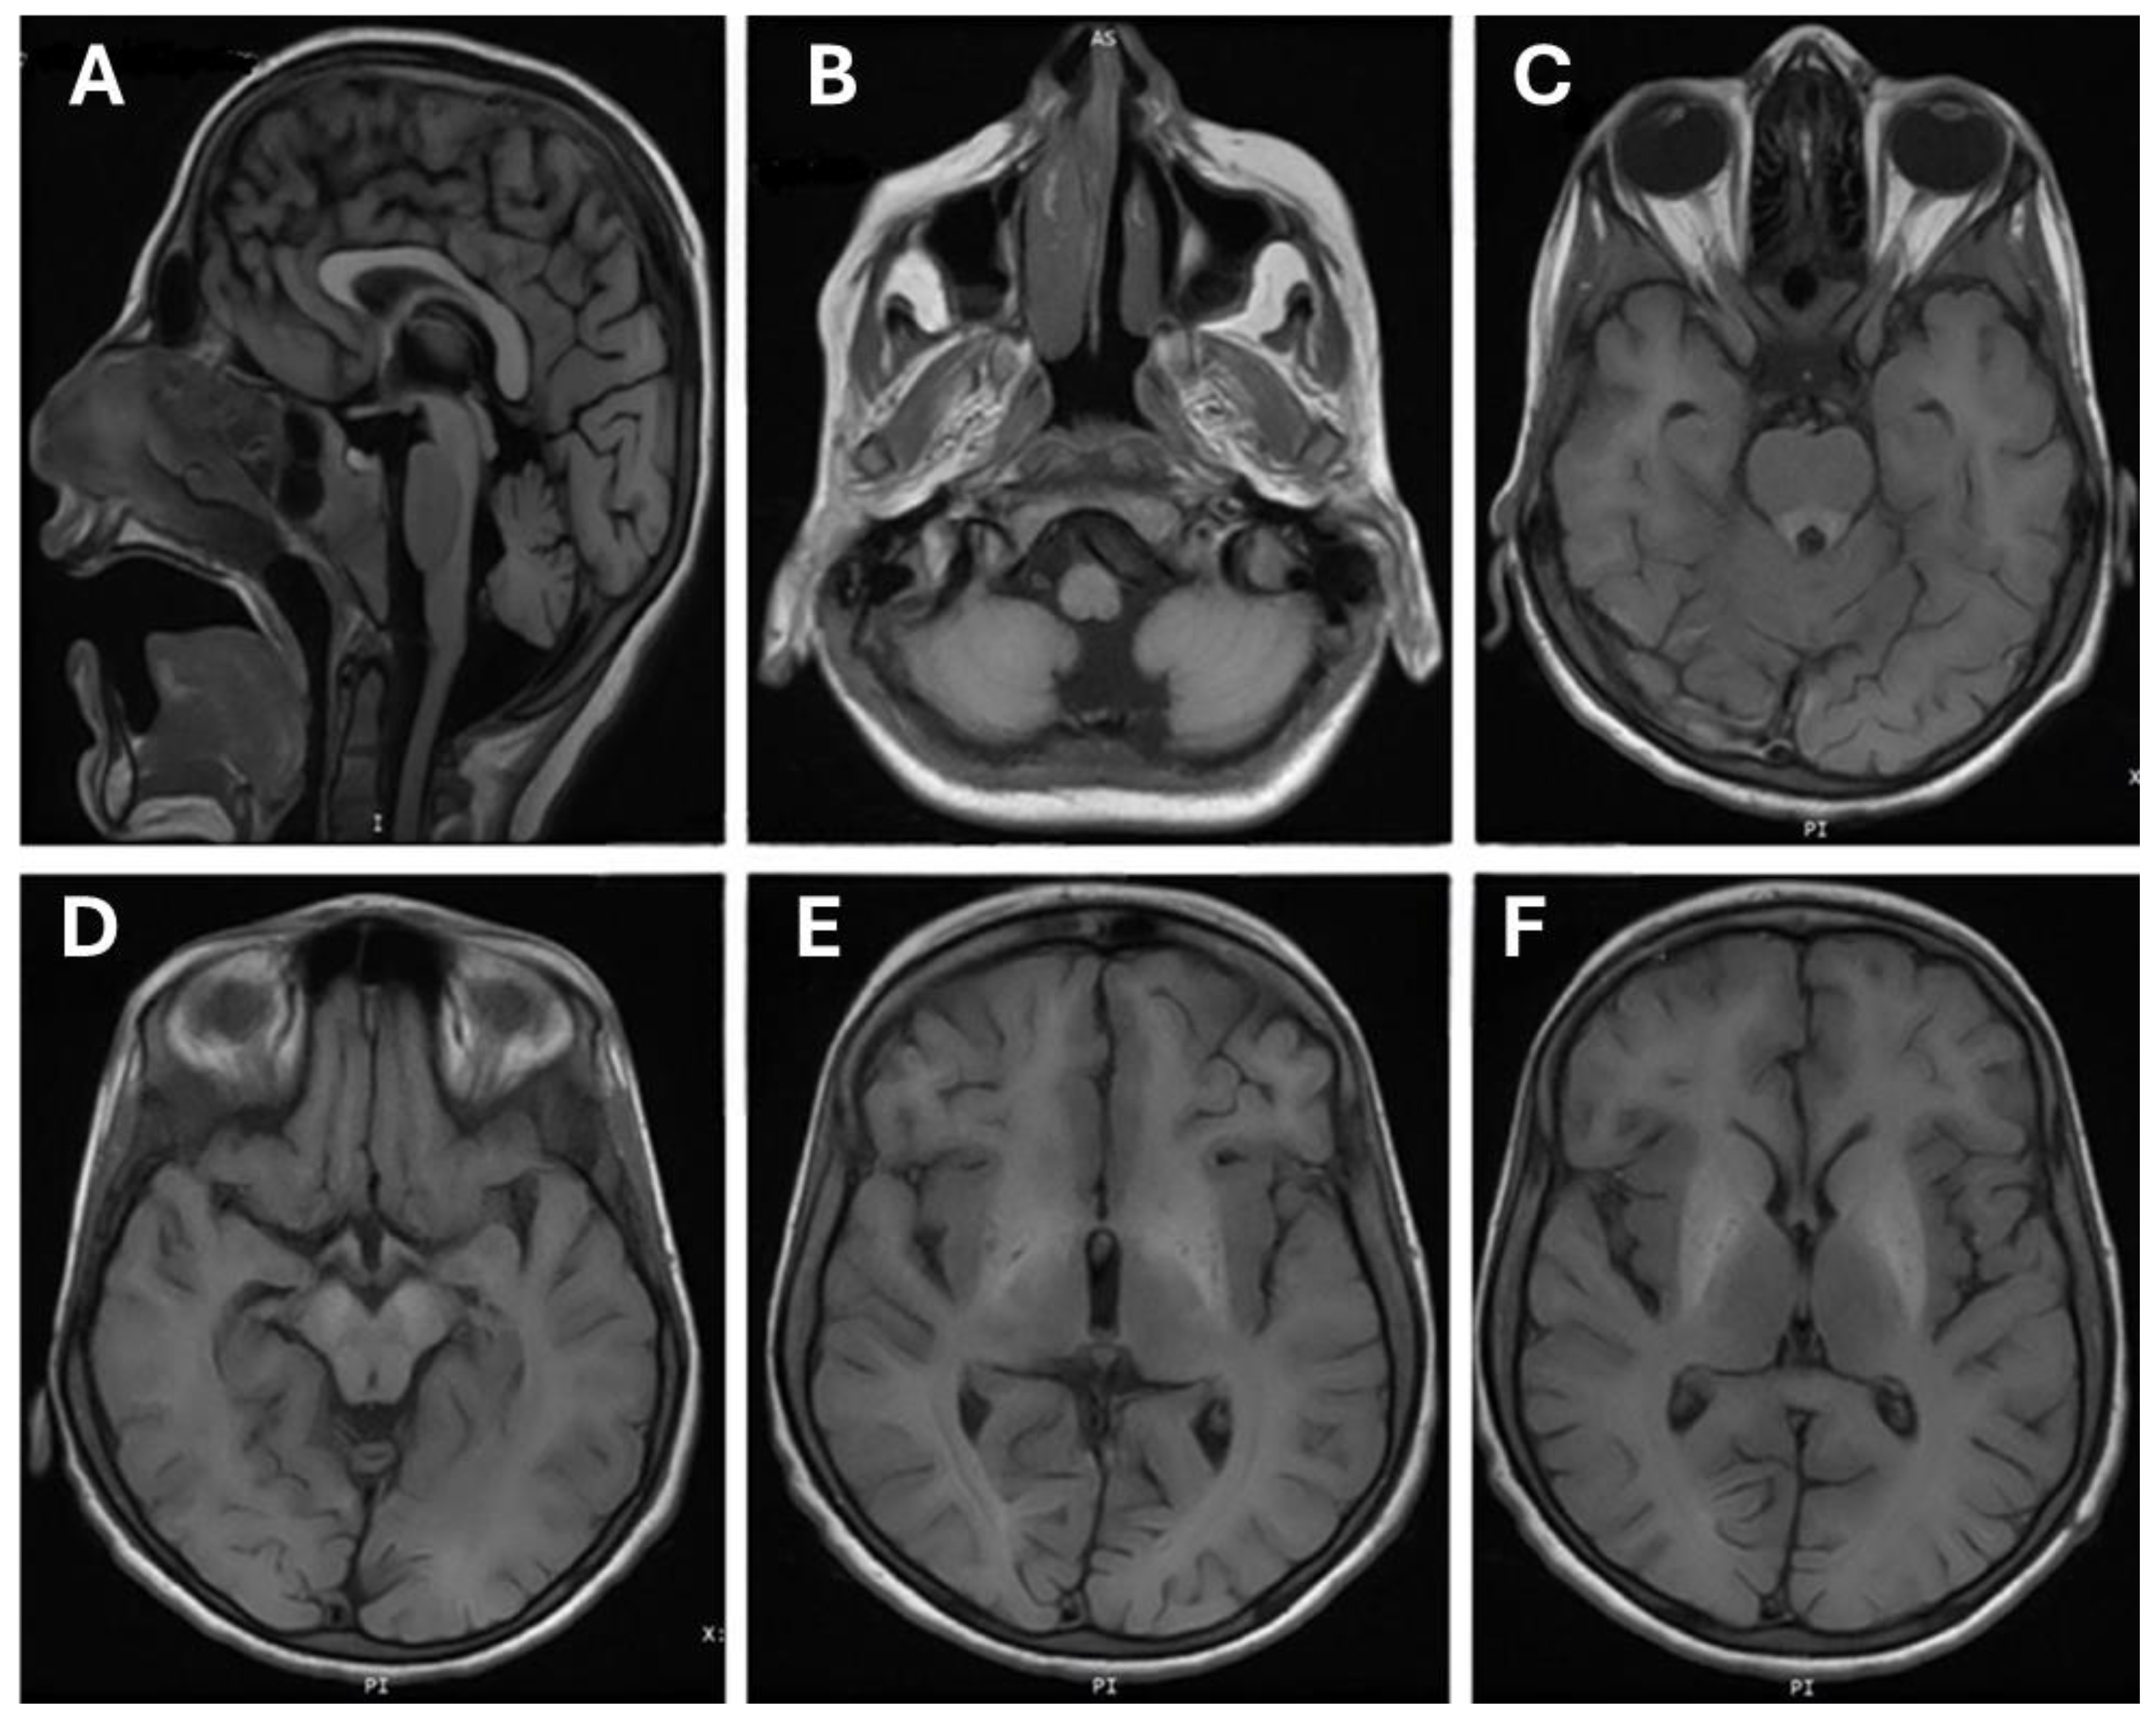

3.2. Brain MRI Finding